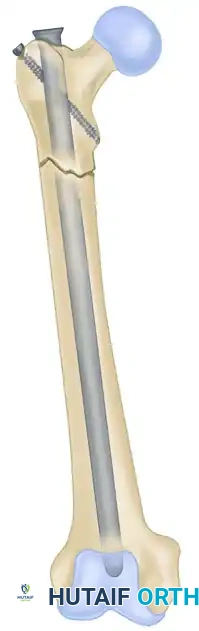

Cephalomedullary Nails

Cephalomedullary nails feature a centromedullary diaphyseal portion but include specialized proximal geometry that permits robust screw fixation up into the femoral head and neck. They are the implant of choice for subtrochanteric fractures and ipsilateral femoral neck/shaft fractures.

* Examples: The Küntscher Y-nail, the Zickel subtrochanteric nail, and modern proximal femoral nails (PFNA, Gamma nails).

* Femur: The traditional entry point is the piriformis fossa, which is perfectly in line with the central axis of the medullary canal. Alternatively, a greater trochanteric entry point can be used with specifically designed trochanteric-entry nails (which feature a proximal lateral bend).